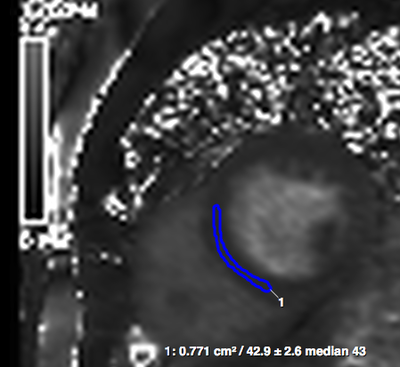

The Institute for Experimental and Translational Cardiovascular Imaging is part of the Medical Faculty of Goethe University Frankfurt, Frankfurt am Main. The institute is dedicated to translational clinical research of cardiovascular imaging biomarkers bringing the best imaging methods into clinical practice to improve patient outcomes. The Institute’s Clinical Trial Unit supports our research and our research partners with the planning, coordination and execution of non-commercial clinical trials (investigator-initiated research studies) either as the study sponsor or a cooperative partner providing imaging core lab services and quality control. This undertaking is made possible due to the support of and cooperation with our funders.